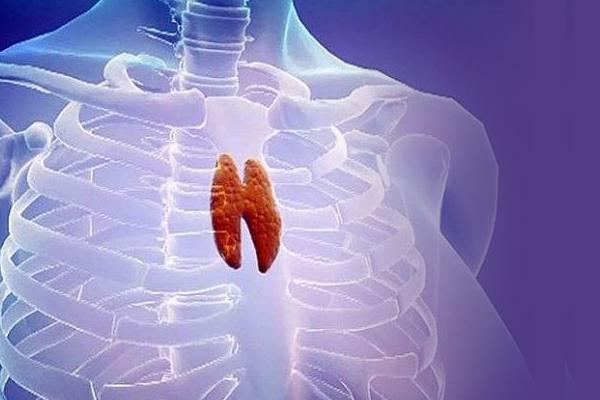

Фотографии вилочковой железы тимуса: структура и функции